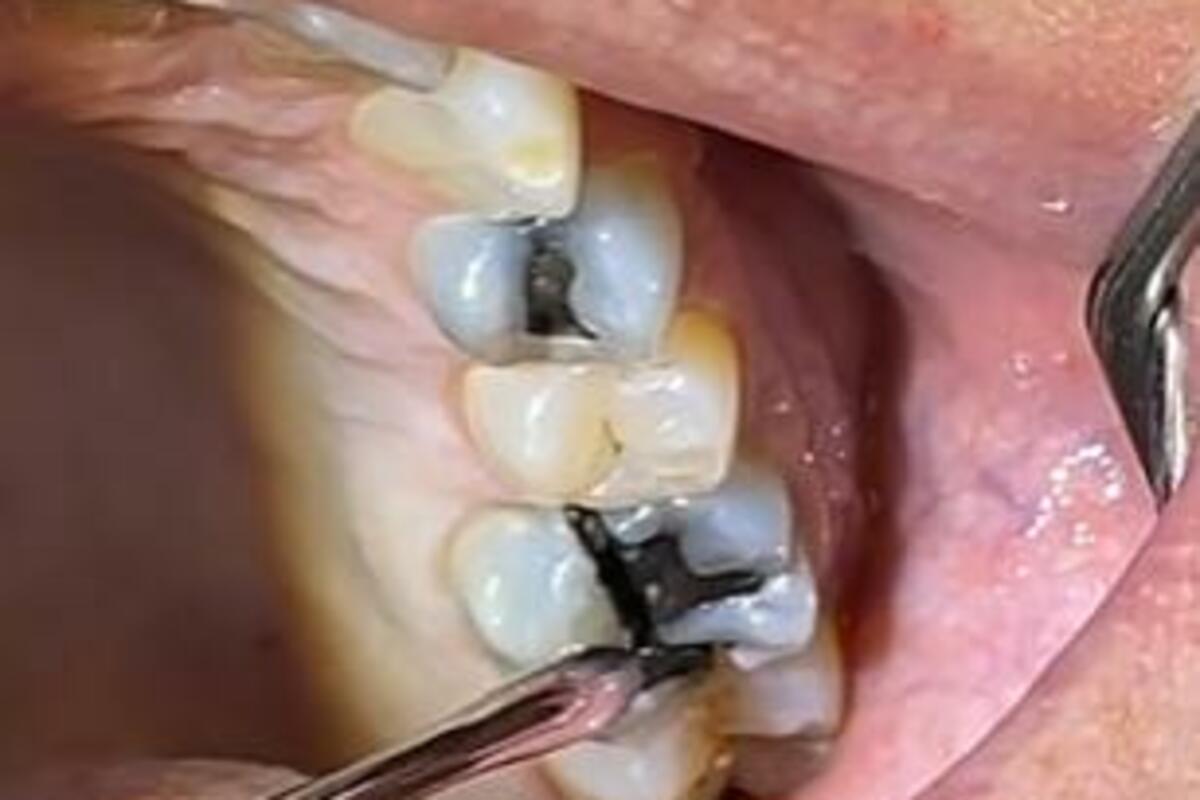

Taj stomatolog je objasnio da su zubi njegovog pacijenta popucali od žvakanja leda. Na zastrašujućem snimku vidi se potpuno uništena gleđ uz kratku i jasnu poruku stomatologa: "Ne žvaćite led, momci!“

Led je polomio zub ovog pacijenta i potpuno ga uništio.